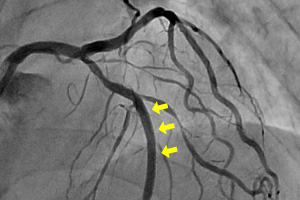

冠動脈(左冠動脈)造影検査

ステント治療後